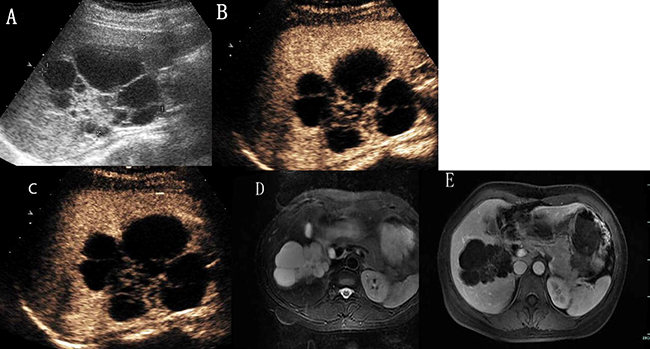

Figure 5: Hepatic hemangioma with septa enhancement in all vascular phases. (A) Ultrasound revealed a mix-echoic mass comprised of a multilocular cystic part in the periphery and a stellate echogenic part in the centre. (B) and (C) CEUS showed isoenhanced with septa and stellate part, no enhancement with cystic part. (D) The lesion showed bright signal intensity on T2-weighted MR images. (E) On enhanced magnetic resonance, the septa part enhanced with contrast and the periphery cystic part was not enhanced.

Hepatic hemangiomas are being detected more frequently than before because of widespread application of routine ultrasound screening. Pathologically, hemangiomas are composed of many endothelium-lined vascular spaces separated by fibrous septa, and the collective size of their constituent vascular spaces may vary [9]. The differentiation of hemangiomas from other hepatic tumors is of great importance. CEUS has markedly improved the accurate diagnosis of hepatic hemangiomas, which is now possible in about 95% of cases [10]. It can provide diagnosis of hemangioma in most cases without requiring further investitation [11]. However, when the enhanced pattern was atypical, it may cause some uncertainty. Familiarity with the atypical appearance of hepatic hemangiomas on US and CEUS will increase the rate of correct primary diagnosis before surgery and histologic examination. In the present study, 11 hemangiomas showed washout in the delayed or portal phase, a common characteristic of them described in this series was their peripheral location on grayscale ultrasound, in one case near Glisson’s capsule. Hemangiomas showed hypoenhanced compared to the adjacent liver parenchyma in the delayed phase, just like subtypes (i), were reported by several authors [12, 13, 14]. The mechanisms of washout had several hypotheses, most researchers [12, 13] believed that this probably occurred because of microbubble rupture due to prolonged insonation, which was not adequately compensated because of progressive hemodilution of contrast agent and a slow blood flow in these lesions. Most hemangiomas showed washout in the delayed phase were located in the liver sub-capsule, and some near Glisson’s capsule [12, 14], we had the same situation in the study presented. Giannetti A et al. thought that hemangioms with arteriovenous and arteriosinusoidal shunts may washout in the early portal phase, which may have caused rapid elimination of contrast agent [14]. Hemangiomas with washout in the delayed or portal phase need differentiation from malignant liver tumors, especially metastasis. Bhayana et al. believed that the differential diagnosis between these lesions and metastases should be based on the time required for the elimination of microbubbles, which occurs much more rapidly in metastases [13]. During these 11 hemangiomas, 7 cases underwent contrast-enhanced magnetic resonance (CEMR), washout was not seen in all the cases. Magnetic resonance (MR) contrast agents had an extravascular equilibrium phase, and the interstitial portion of the hemangioma was filled during the delayed phase of the examination, which resulting in a hyper-isointense appearance compared with the adjacent parenchyma [15]. In our experience, hemangiomas with atypical appearance on CEUS due to washout may be diagnosed on the peripheral nodular enhancement and progression of centripedal filling in the arterial and portal phases of the examination. Besides washout in the late phase, the next most common atypical appearance of hepatic hemangiomas on CEUS was just peripheral enhancement without the progress of fill-in in all the vascular phases, just like subtypes (ii) and subtypes (iii). Since thrombo-haemorrhagic episodes, cystic degeneration, fibrosis or hyalinisation and calcium deposit may occur. Peripheral nodular enhancement was the typical feature of hemangioma in the arterial phase, if the peripheral nodular sustained hyper-isoechoic, it was helpful to make the diagnosis of hepatic hemangiomas. However, peripheral circular enhancement may cause some uncertainty, for it can be seen in other benign and malignant hepatic tumors, such as metastasis and inflammation. Without contrast enhancement throughout the whole enhancement period, just like subtypes (iv), is a very rare appearance of hemangioma, K. Mitsudo [16] reported a case of liver cavernous hemangioma which had multiple spotty calcifications arranged like a wreath and showed no enhancement on contrast-enhanced tomography. They misdiagnosed it as an old pyogenic abscess or cystadenoma preoperatively. Case 19 in our study was a 32-year-old man, he had a hyperechoic mass measuring 3.5 cm*3.1 cm in hepatic segment VII, which had multiple spotty calcifications and clear margin. Both CEUS and CEMR showed no contrast enhanced, on T2 weighted MR imaging, high signal intensity with fluid–fluid level could be seen (Figure 4). CEUS diagnosed it with old pyogenic abscess and CEMR diagnosed it with hepatic cyst. Core needle biopsy was performed and histopathologic examination revealed dialated blood vessels and collagen. The patient himself asked for surgery, so a partial hepatectomy was performed. The histological diagnosis was cavernous hemangioma with thrombosis and calcification. Hepatic tumors without contrast enhancement should not preclude the diagnosis of cavernous hemangioma. Multicystic appearance is very rare in atypical features of hepatic hemangiomas and several cases had been reported [17, 18, 19]. Case 20 in our study was a 48-year-old woman, she had a mix-echoic mass measuring 7.8*6.7*6.9 cm in the right liver. It was comprised of a multilocular cystic part in the periphery and a stellate echogenic part in the centre. On CEUS, septa and stellate part showed isoenhanced compared with the adjacent parenchyma, cystic part showed no enhancement through all vascular phases. On MR images, the lesion showed bright signal intensity on T2-weighted images, low signal intensity on T1-weighted images. Findings of CEMR was same as CEUS (Figure 5). Both CEMR and CEUS diagnosed it with biliary cystadenoma. The patient underwent partial hepatectomy and the histological diagnosis was multicystic cavernous hemangioma. The pathogenesis of the cystic change of hemangioma is not clearly understood, apoptosis had been proposed as one of the cause [20]. A predominantly cystic mass also should not preclude the diagnosis of cavernous hemangioma. Centrifugal (inside-out) enhancement was a more rare appearance of hepatic hemangioma. This enhancement pattern on dynamic contrast-enhanced computed tomography, CEMR and CEUS had also been reported [21, 22]. Case 21 in our study was a 50-year-old woman, she had a hypoechoic mass in the left liver measuring 2.9*2.7 cm. On CEUS, there was a central enhancing foci in the arterial phase and followed by a centrifugal enhancement in the portal-venous phase, it washed out in the late phase. The lesion presented as hypointense on unenhanced T1 weighted MR images and markedly hyperintense on T2 weighted MR images. CEMR confirmed the central enhancing focus in the arterial phase followed by a centrifugal enhancement in the portal-venous phase, but showed incomplete fill-in not wash-out in the late phase (Figure 6). Both CEUS and CEMR diagnosed it with hepatic carcinoma. The patient underwent partial hepatectomy and the histological diagnosis was cavernous hemangioma. This centrifugal (inside-out) enhancement should be differentiated from the central starlike fill-in enhancement which have a very high specificity for characterising focal nodular hyperplasia (FNH). Focal areas of intralesional enhancement were also observed in liver malignancies such as primary hepatic carcinoma and primary hepatic angiosarcoma [23]. In order to rule out malignancies, further investigation like core needle biopsy may be needed. Case 22 in our study was a 51-year-old woman, she had two hypoechoic masses in the liver, the larger one measuring 3.5*2.9 cm was located in hepatic segment VI, the other one measuring 3.3*2.8 cm was located in hepatic segment IV, on CEUS, the lesions showed very slow spoke-wheel pattern and were hypoenhanced throughout the vascular phases. On T2 weighted MR imaging, high signal intensity with fluid–fluid level could be seen, they presented as hypointense on unenhanced T1 weighted MR images, CEMR showed slightly rim enhanced in all vascular phases (Figure 7) and diagnosed it with metastasis.Core needle biopsy was performed in tumor that located in hepatic segment VI, and histological diagnosis was cavernous hemangioma. The patient had been followed up for more than two years. This slow spoke-wheel enhancement should also be differentiated from FNH which was always quickly enhanced and hyperechoic in arterial phase. Among the atypical appearance of hepatic hemangiomas, slow spoke-wheel pattern was extremely rare, there were few such reports available that describe this appearance.